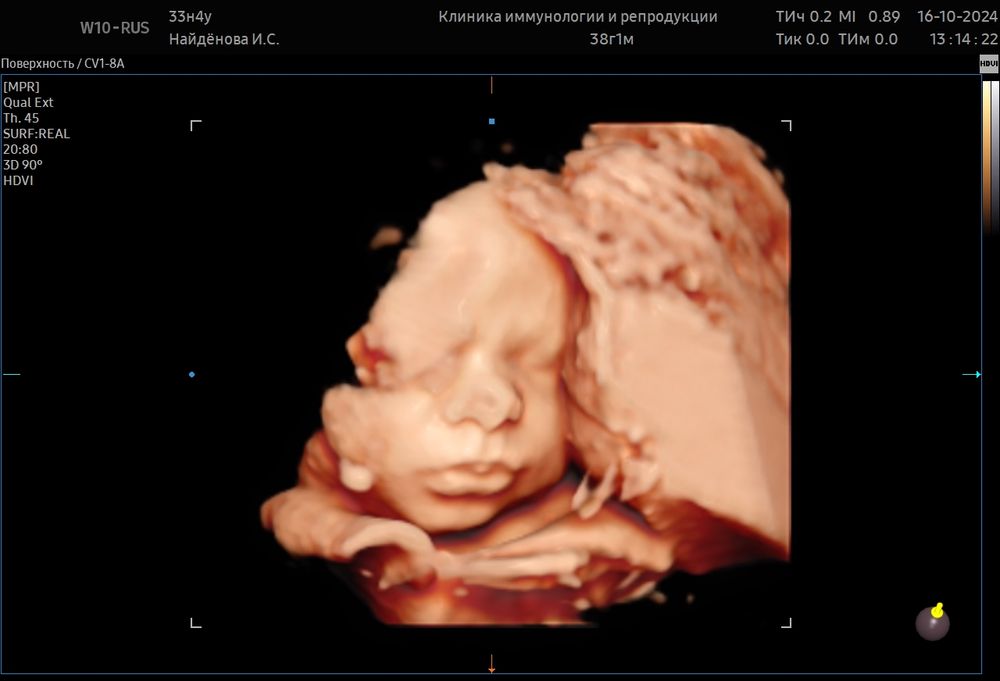

Скрининг , фото

На первом фото и нижнюю вижу, у нас наоборот нижняя губеха большая, а верхняя маленькая, но это в папу.

bravo gun, да копия узи Изображение

у меня оба ребенка подсасывали нижнюю губку внутрь пока зубов не было и тоже казалось что верхняя губа больше)) Но вообще тут же ракурс сверху, еще и датчик и вода искажают немного.

Это так снимок просто получился, ручкой прикрыла губки

Это большой пальчик руки 😁